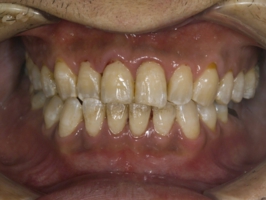

プラークコントロールの前後で、歯肉の変化を見てみましょう

初診時です。歯肉が腫れ、一部歯石も見えます。写真からは伝わりませんが口臭もありました。